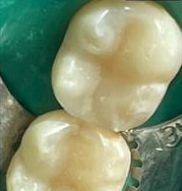

7 работ в портфолио